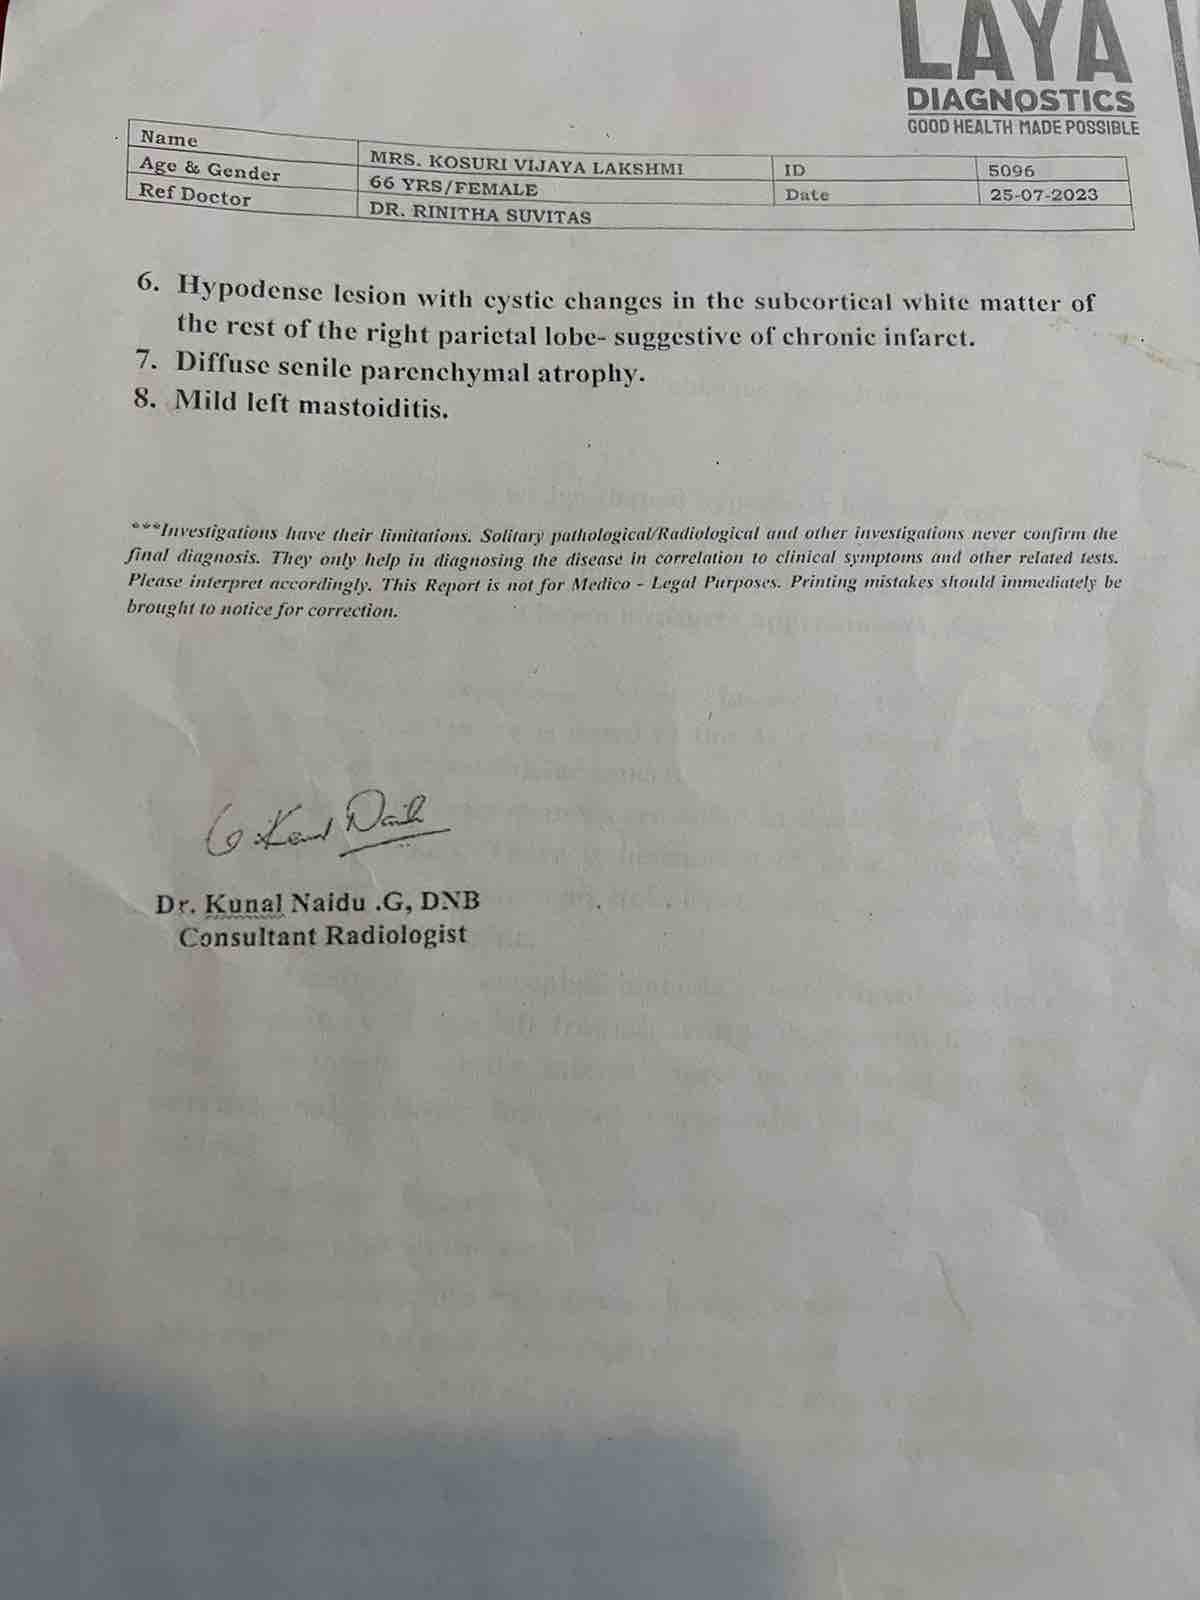

We are reaching out to you today with a heavy heart and a plea for help. Our beloved 66-year-old mother K VIJYA LAKSHMI, has been facing an incredibly challenging journey since 16th May when she had brain stroke & underwent emergency brain and abdomen surgery. Her recovery has been a rollercoaster of ups and downs.

During her hospitalization, she endured multiple complications, including respiratory distress, recurrent severe infections, and even seizure-like activity. Through it all, she has shown immense strength and determination. Still she require three more surgeries to stand on the path of recovery.